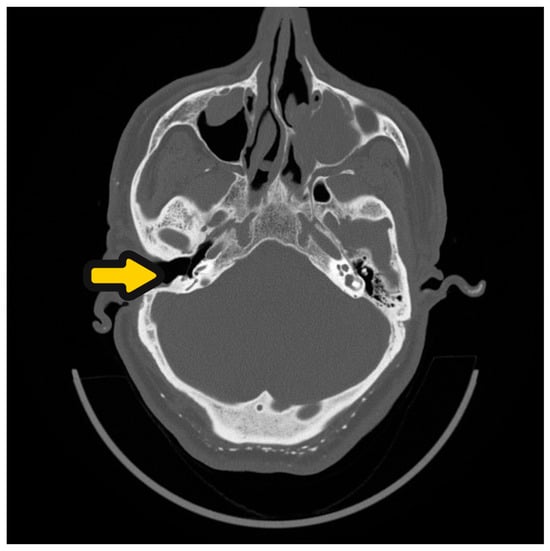

Regarding the filling used for SP, Rambo reported the use of the temporalis muscle for obliteration, while in 1976, Gacek presented the use of abdominal fat and an inferiorly based muscle pedicle [4]. Brizgalis suggested that the temporalis muscle flaps in SP need to be small enough to allow overfilling of the large cavity to compensate for its gradual postoperative shrinkage [1]. However, Bartells has reported complaints of severe pain above the ear and cases of necrosis following temporalis muscle flap creation [16]. On the other hand, free tissue grafts, such as abdominal fat, cartilage or bony palate, lack vascularity and are subject to resorption [17]. Particularly, Yung noted postoperative infections and fat necrosis in a number of patients obliterated with abdominal fat [18], which was consistent with our findings and that of other studies. Moreover, Bernardeschi reported that 8% of minor complications at the donor site were abdominal hematomas [19]. Giulia D’Angelo similarly presented one case of seroma and one case of hematoma in 32 patients who underwent SP with abdominal fat grafting [20]. In these cases, other sources of free grafts are recommended as an alternative, such as fat or temporalis muscle. In 1996, Chenay introduced an interesting concept of using the pedicled TPFF for cavity obliteration in the SP procedure [21]. TPFF has been found to have a beneficial effect on the healing and acceptance of free skin grafts for mastoid obliteration due to its resistance to bending and compression as a result of the large diameter of the pedicle vessels [17,22]. Therefore, based on the results of Chenay and Yung, the author of this article used TPFF for obliteration after the SP procedure [18,21]. However, problems regarding the flap’s maximal evaluable volume for cavity obliteration and postoperative muscle shrinkage were noted. The TPFF, in particular, has a flat surface (150 cm2) and is the thinnest in the human body pedicle flap (2 mm), only providing a volume of 30 mL, which may be a limitation for its use. For this reason, we used up to 8 mL IPRF+ injections to increase the flap volume, given its high vascularity and regenerative ability [23]. IPRF+ is a second-generation, fully autologous, blood-derived biomaterial with a three-dimensional fibrin meshwork that is widely used in dentistry, dermatology, and orthopaedics [24]. Furthermore, IPRF+ preparation is easy and requires a basic instrument set without biochemical blood handling [25]. IPRF+ is widely used due to its high regenerative potential from its plates and lymphocytes, which deliver growth factors. Moreover, it consists of type-1 collagen, making it useful in various surgical conditions [24,26], and its anti-inflammatory role in wound healing is also essential for postsurgical recovery [27]. In summary, it is important to note the advantages and disadvantages of the commonly used SP obliteration materials. Although fat has a high volume, it has poor vascularization and has a tendency for inflammation and absorption (Figure 8). On the other hand, the temporalis muscle flap has a lower volume availability that is needed for rotation, which creates a situation of incomplete coverage of the receiver–stimulator. The flap also has a tendency to shrink, but it has good vascularity, providing efficient anti-inflammatory resistance. Lastly, TPFF injected with IPRF+ demonstrates all the advantages of these two reconstructive materials, while providing the best cosmetic effect.

Figure 8.

Patient 12 months after SP with external auditory canal closure and fat obliteration. Yellow arrow shows a depression caused by absorption of fat.